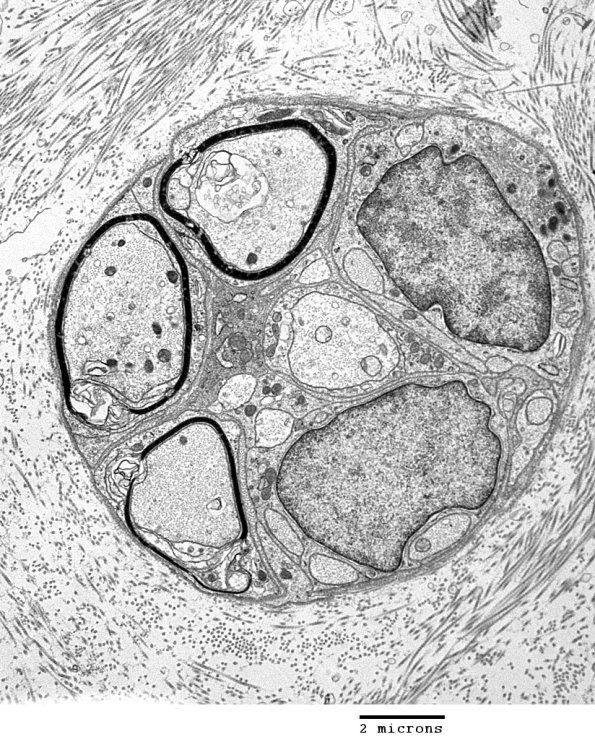

Additional examples of traumatic axonal injury. (Electron micrographs)